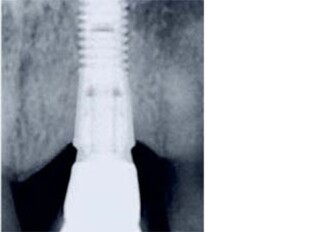

New, five-year data confirm maintained bone levels and biological sustainability with OsseoSpeed implants

New five-year data on OsseoSpeed implants (ASTRA TECH Implant System) show stable soft tissue and maintained bone levels from implant placement and implant loading, confirming an average bone level ...